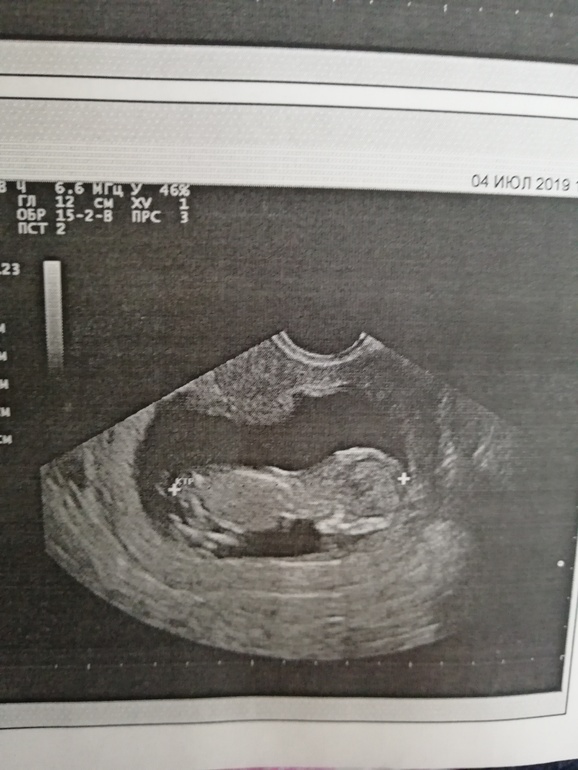

Добрый вечер мамуськи) сделала и я сегодня долгожданный 1 скрининг. Ура)) 12 нед. и 5 дней. ПДР 11 января 2020г. Вес 55 г. Женщина которая делала УЗИ, мне не очень понравилась, слова не вытянишь. Я как и многие тут не понимаю снимки, точнее не вижу кто, мальчик или девочка)) Но знаю точно, что в группе есть девочки которые понимают. Помогите понять пожалуйста)) кого вы видите.

По 1му фото предположу пацана. Но не факт. На остальных вообще ниче не видно.

На фото к сожалению не видно бугорка. Поздравляю с удачным скринингом. А кровь скоро будет готова? Сколько делают. У нас через неделю скрининг.

К сожалению полового бугорка не видно (

Может ещё фото есть ?